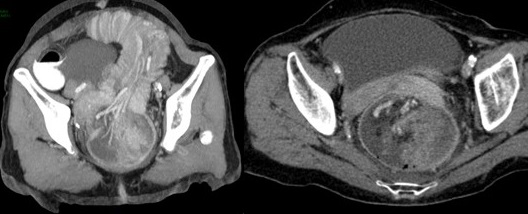

Se presenta el caso de una paciente femenina de 71 años, que ingresa por guardia con dolor abdominal en fosa iliaca derecha y deposiciones diarreicas sanguinolentas. Al examen físico, abdomen blando depresible, con masa palpable, y doloroso a la palpación en FID. En la TC de abdomen y pelvis con contraste oral y EV se observó el pasaje del contraste oral hasta colon derecho. Ángulo derecho descendido de topografía, donde se observa área redondeada de engrosamiento parietal con realce. Distalmente se observa intususcepción, que compromete el resto de colon hasta el recto con ligero realce parietal en dichos segmentos en relación con hiperemia. No se observó dilatación de asas delgadas.

En la TC de abdomen y pelvis con contraste oral y EV se observó el pasaje del contraste oral hasta colon derecho. Ángulo derecho descendido de topografía, donde se observa área redondeada de engrosamiento parietal con realce. Distalmente se observa intususcepción que compromete el resto del colon hasta el recto, con ligero realce parietal en dichos segmentos en relación con hiperemia. No se observa dilatación de asas delgadas.